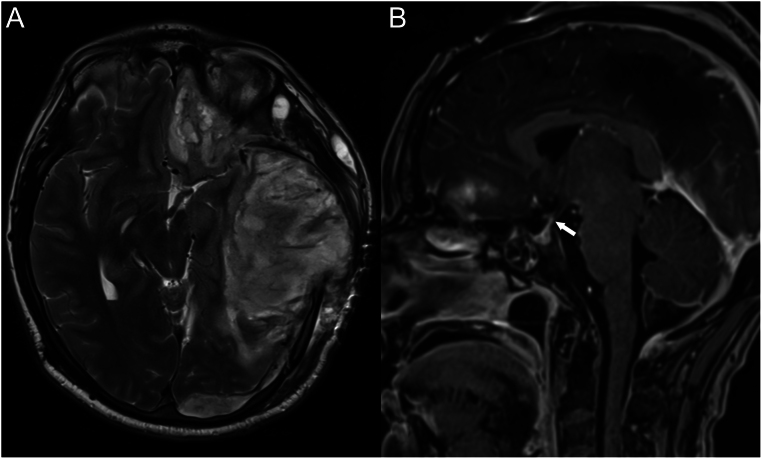

Summary: Delayed arginine vasopressin deficiency (AVP-D) can present in patients following traumatic brain injury (TBI) and may occur years after the trauma, presenting with nonspecific symptoms. The objective of this case is to highlight the importance of considering the delayed onset AVP-D in patients with a history of TBI. We report a case of a patient who had sustained severe traumatic brain injury 8 years before and who presented with polydipsia, behavioural disorder and frequent falls during the last 3 months. The diagnosis of AVP-D was confirmed by water restriction with a positive response to desmopressin, and pituitary MRI showed an absent spontaneous posterior hyperintensity on T1WI. Follow-up confirmed permanent diabetes insipidus as well as a suspected anterior pituitary deficiency. Pituitary dysfunction occurs following TBI and is correlated with severity. As in our case, symptoms are generally non-specific and are difficult to explore given the patient's neurologic sequelae. MRI 8 years post trauma showed changes in pituitary morphology. Some authors have proposed the need for active screening of post-TBI patients. This case highlights the need for clinicians to be aware that AVP-D can occur years after traumatic brain injury.